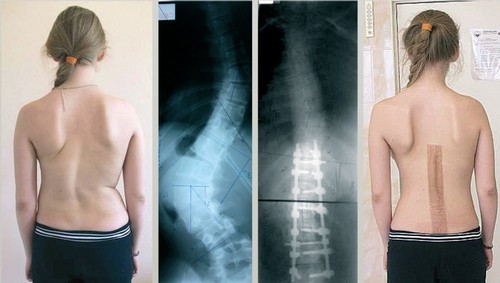

Для начала пациент проходит детальное обследование. Обязательной является рентгенография пораженных сегментов позвоночника в разных проекциях. Она помогает установить степень патологических изменений и подобрать тип хирургического вмешательства.

В первые сутки после операции необходимо соблюдать постельный режим. Допускаются минимальные движения верхними и нижними конечностям. Вставать можно только через 7 дней. В это же время проводится контрольное рентгенологическое исследование и начинаются занятия ЛФК. Массаж ног осуществляют на 7–10 сутки после операции на спину. После устранения сколиоза 4 степени показано ношение поддерживающего корсета .

Повторные рентгеновские снимки или КТ назначают через 3 месяца.

Большинство манипуляций выполняется эндоскопическим методом с минимальным повреждением тканей. Исправление сколиоза осуществляет путем внедрения фиксирующих устройств. Они закрепляют сегменты в нормальном положении и устраняют их патологическую подвижность. Металлические стержни могут быть подвижными или статичными. Первые применяются при лечении сколиоза у молодых людей, у которых формирование скелета еще не завершилось. Вторые отличаются более низкой ценой и используются при искривлении позвоночника у взрослых.